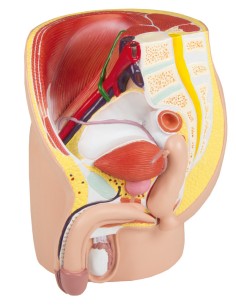

Dal cranio in 22 parti con incastri magnetici ai modelli di colonna vertebrale, da quelli di articolazioni a quelli di cuore, ogni pezzo della nostra collezione è progettato per un’immersione totale nello studio dell’anatomia umana. I nostri modelli, realizzati tramite scansioni di ossa vere, garantiscono un’esperienza tattile autentica e una fedeltà di peso quasi identica agli originali.

Essenziali per studenti e professionisti, i nostri modelli anatomici sono strumenti didattici che permettono di osservare le strutture anatomiche con precisione, eliminando la necessità di dissezioni o studi invasivi. Sono inoltre utili per spiegare ai pazienti le patologie, rendendo la comunicazione più efficace e risparmiando tempo prezioso.